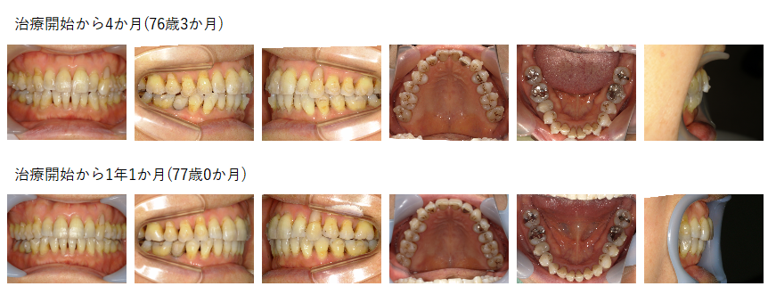

【治療例】初診時年齢:75歳9か月 / 性別:女性 / 主訴:歯がガタガタで食べ物が詰まりやすい

治療の概要:この症例は、マウスピース型(アライナー型)矯正装置(インビザライン®)を用いて非抜歯で治療した症例である。

補綴物が多く認められたため、補綴物やアタッチメントの脱離をしたものの比較的短期間で治療を終えた。

主訴:歯がガタガタで食べ物が詰まりやすい

診断名:アングルⅠ級叢生

使用した主な装置:マウスピース型(アライナー型)矯正装置(インビザライン®)

抜歯/非抜歯および抜歯部位:非抜歯

※上記価格は税込価格です。消費税は10%で表示しております。

※こちらの症例は2022年3月から2023年9月に行った矯正治療です(現在も経過観察中)

治療期間:1年7か月

治療回数:20回

リスクの副作用:歯の移動や抜歯による違和感や疼痛、口内炎、歯肉退縮、歯根吸収が生じることがある